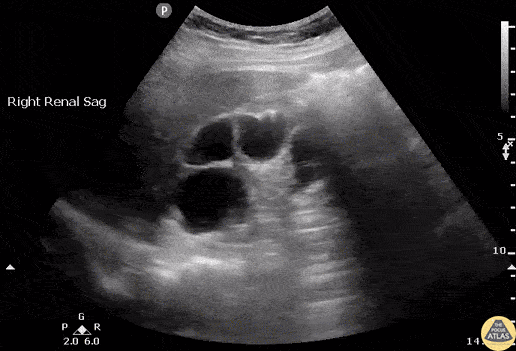

A female presented to the ED with right flank pain, fever, leukocytosis, soft vitals, and dirty urine. Urine culture grew Proteus mirabilis. Bedside ultrasound revealed a bear claw sign with perinephric abscess indicative of xanthogranulomatous pyelonephritis. Image courtesy of Robert Jones DO, FACEP @RJonesSonoEM Director, Emergency Ultrasound; MetroHealth Medical Center; Professor, Case Western Reserve Medical School, Cleveland, OH View his original post here